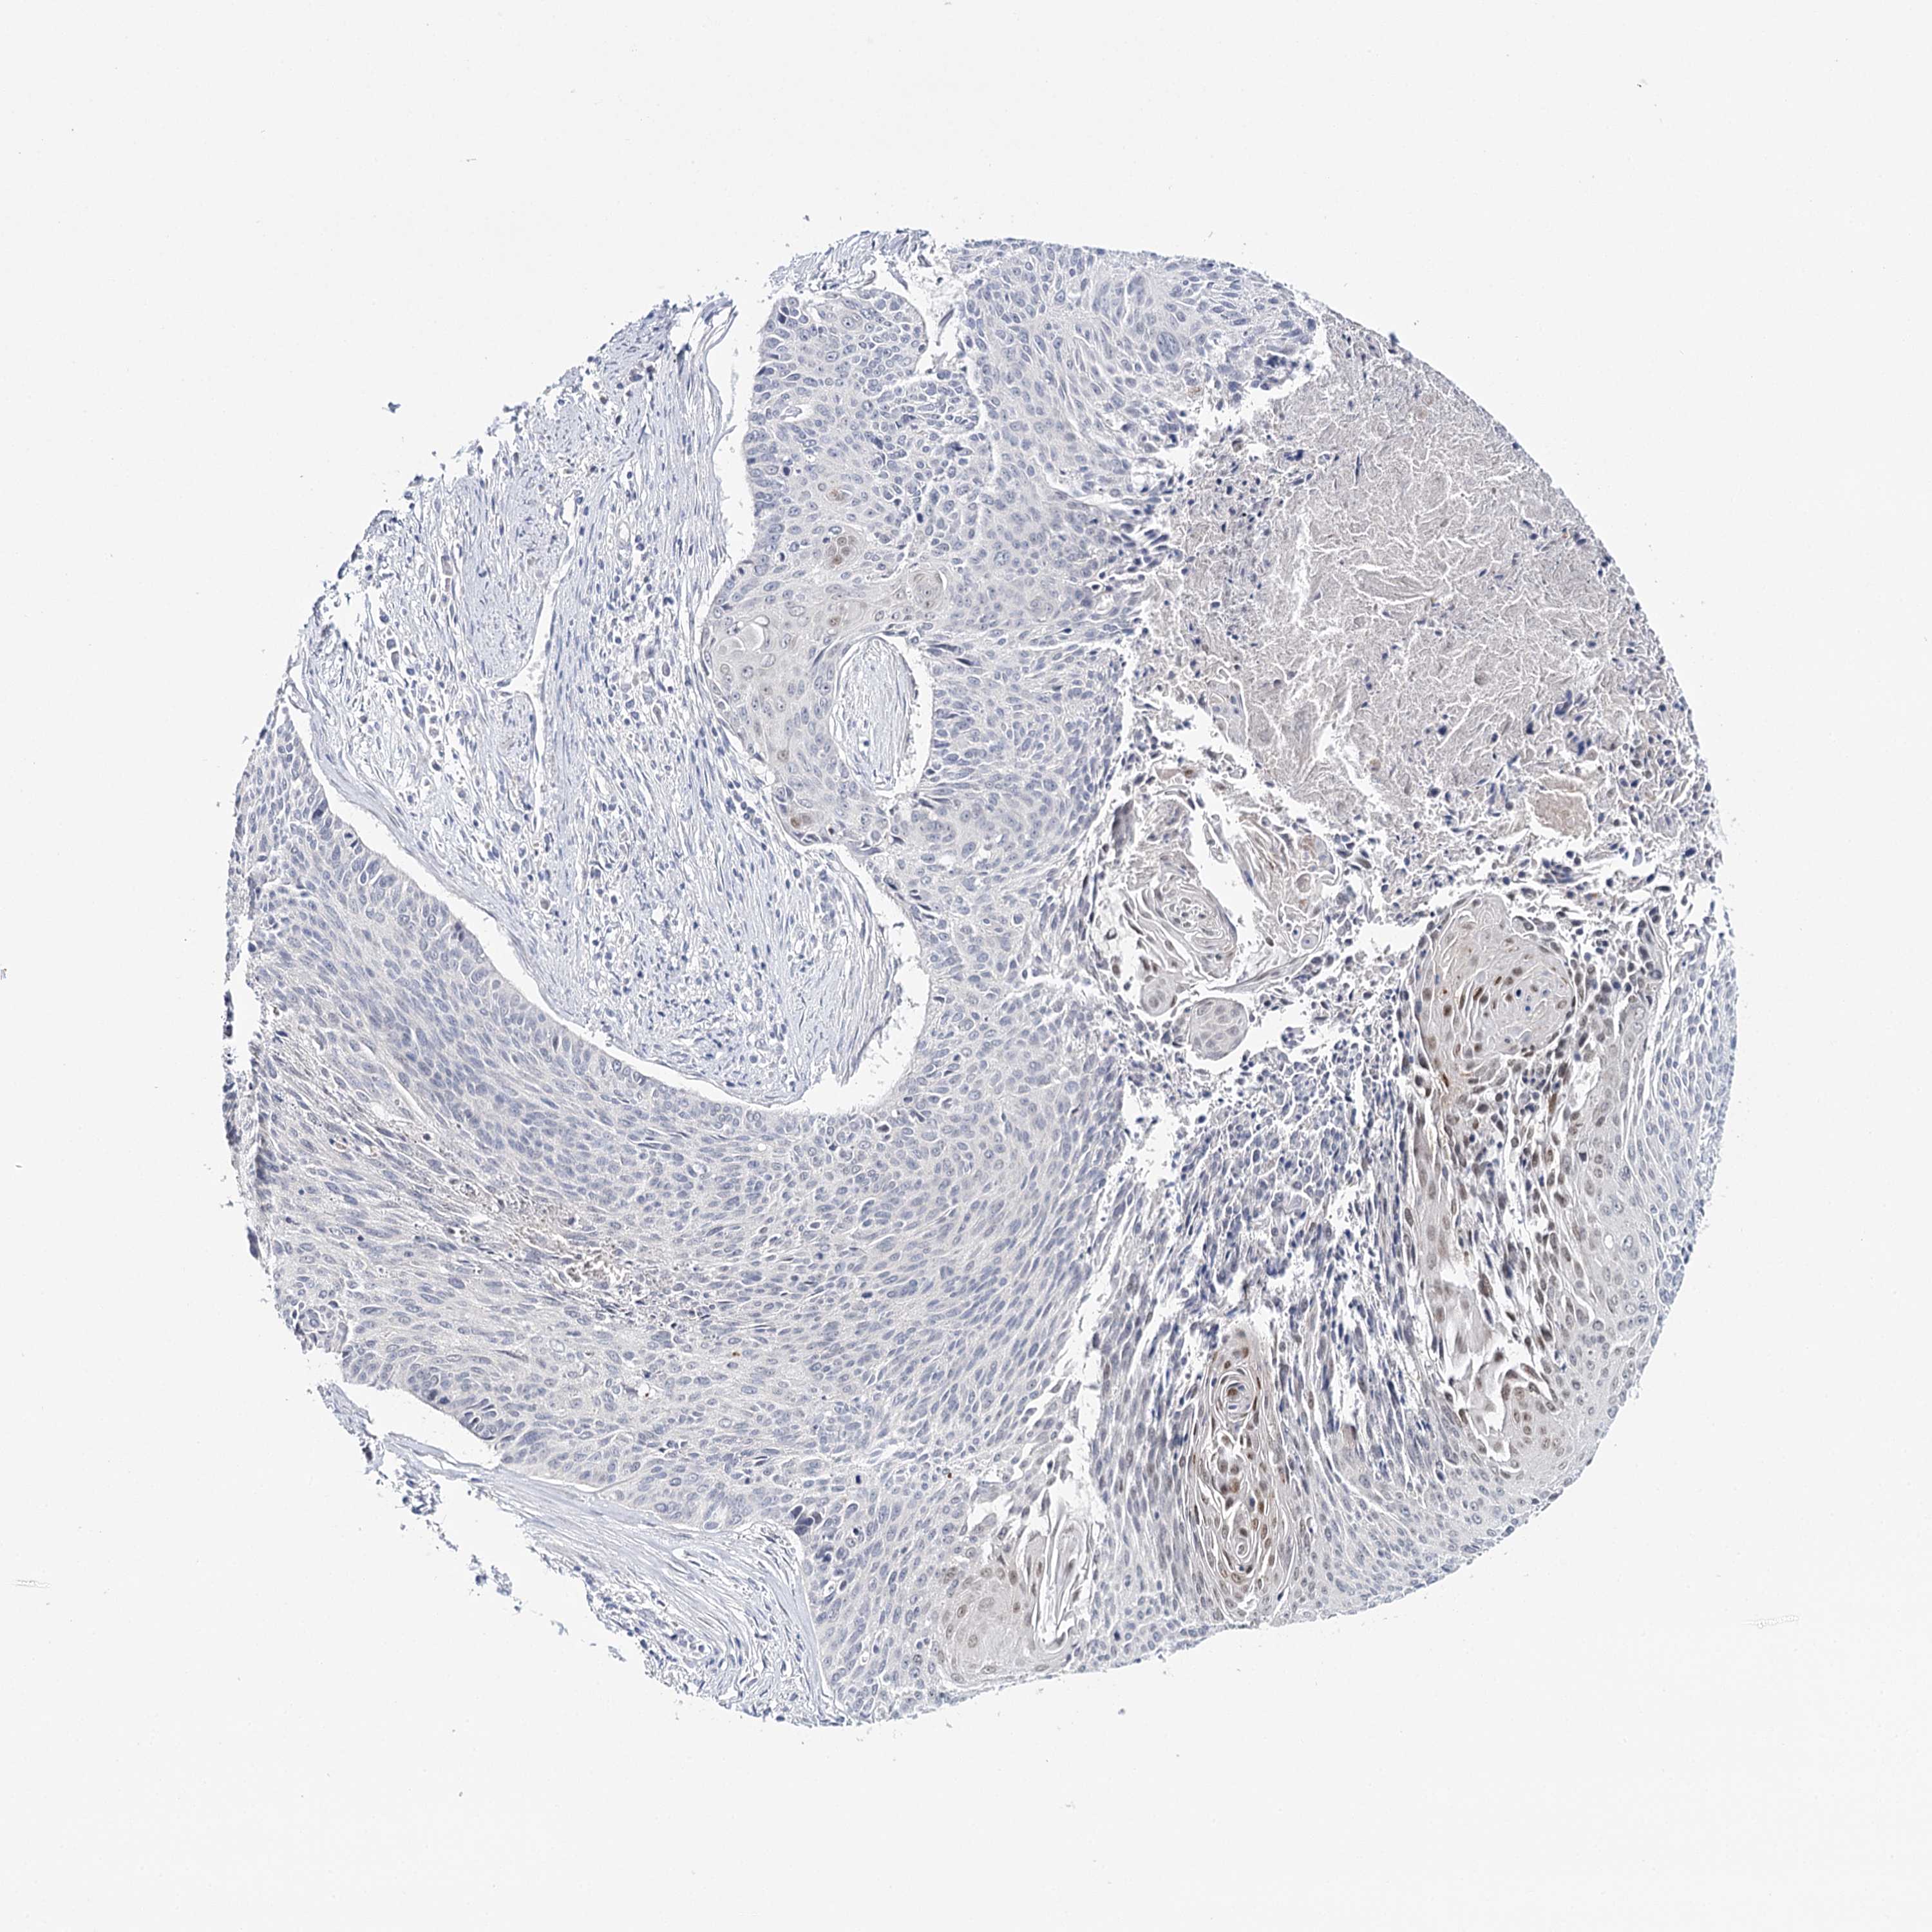

CERVICAL CANCER - Protein expressioni

A mouse-over function shows sample information and annotation data. Click on an image to view it in a full screen mode. Samples can be filtered based on level of antibody staining by selecting one or several of the following categories: high, medium, low and not detected. The assay and annotation is described here.

Note that samples used for immunohistochemistry by the Human Protein Atlas do not correspond to samples in the TCGA dataset.

Antibody stainingi

Antibody staining in the annotated cell types in the current human tissue is reported as not detected, low, medium, or high, based on conventional immunohistochemistry profiling in selected tissues. This score is based on the combination of the staining intensity and fraction of stained cells.

Each image is clickable and will lead to virtual microscopy that enables deeper exploration of all samples and also displays staining intensity scores, fraction scores and subcellular localization as well as patient and tissue information for each sample.

Antibody CAB002973

Antibody CAB039238

Antibody CAB039239

Antibody CAB072876

Adenocarcinoma, NOS

Squamous cell carcinoma, NOS